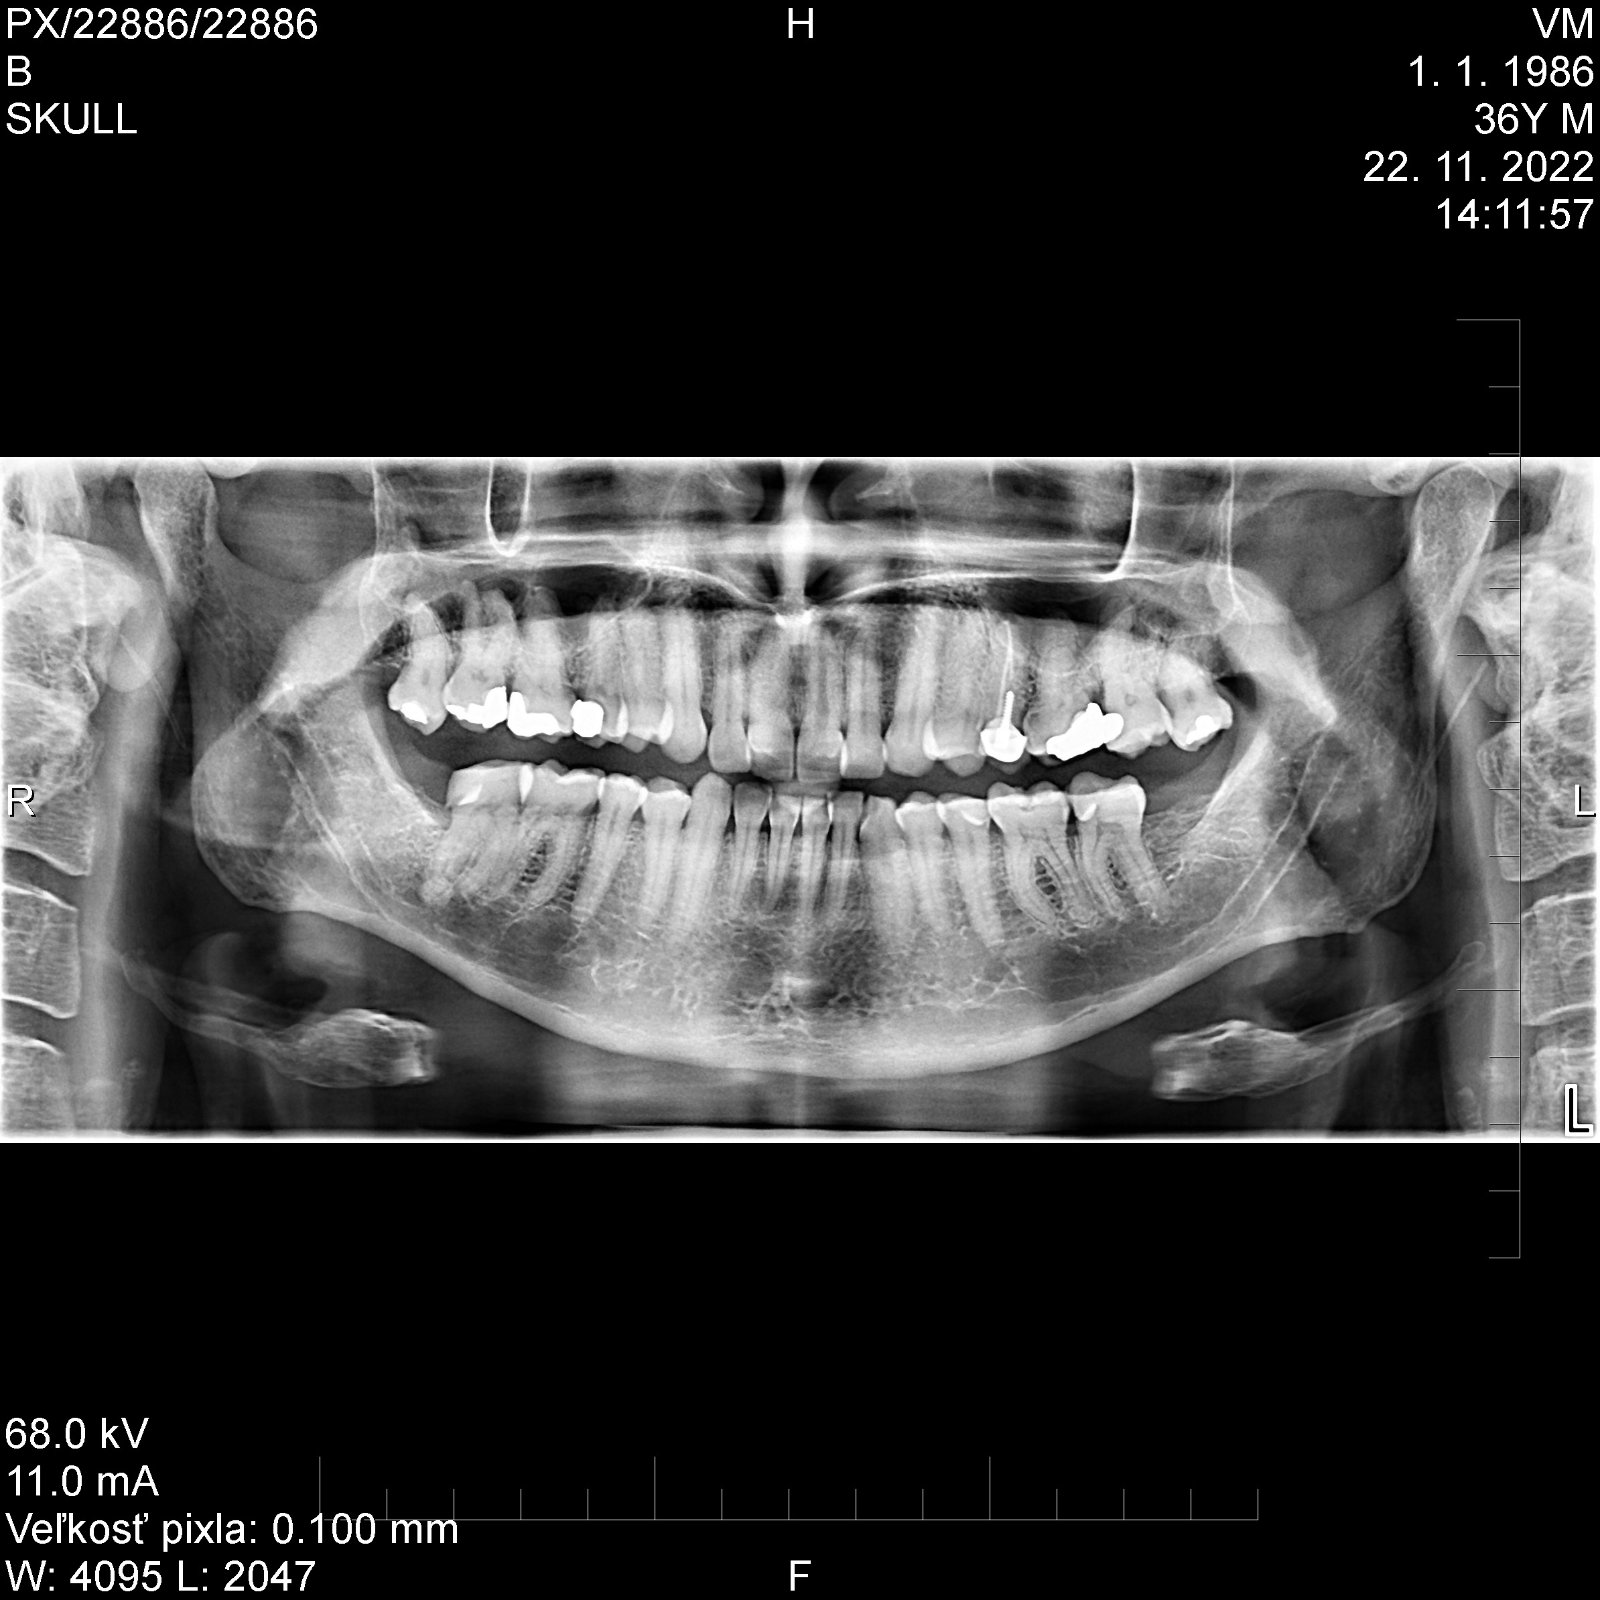

Ahojte. Rád by som sa s vami poradil ohľadom zubára, možno by bolo super, keby sa aj tu nejaký nájde na zhodnotenie môjho snímku zubov. Každý rok pri preventívnej prehliadke mi zubár zahlási cca 3 kazy. Už sa mi tomu nechce veriť, nepociťujem bolesť, zvýšenú citlivosť ani nič podobné, veľa zubov už mám zablombovaných. Zuby sa umývajú každý deň min. ráno a večer + medzizubné priestory. V prílohe prikladám aj pan.snímok, ak by sa tu niekto fundovaný našiel a zhodnotil ho, bol by som nesmierne rád.

@mirec8684 pravdepodobne sa jedna o tieto zuby. Z obrazovky mobilu sa tazko cita. Vpravo 5 hore (na rtg je to ta vlavo) je na 100% kaz a vlavo hore by bolo lepsie spravit mensi snimok. Ono je to aj o zubaroch, ci vedia citat rtg, ci ho vobec aspon robia. A najviac je spravne cistenie zubov. Vacsina ludi co ma kazy sa stazuje na genetiku, pritom realita je taka, ze zla genetika je u menej nez 1% populacie.

@mirec8684 no väčšinu kazov (podľa plomb) mavate práve v medzi zubnom priestore. Zlepšiť techniku čistenia medzi zubných priestorov. Aj ďasná vyzerajú byt dosť ústupene. Pridať návštevu DH aspoň 2x za rok. Zatiaľ mate všetky zuby, to je fajn. Spodné 8 asi neboli ani založené...